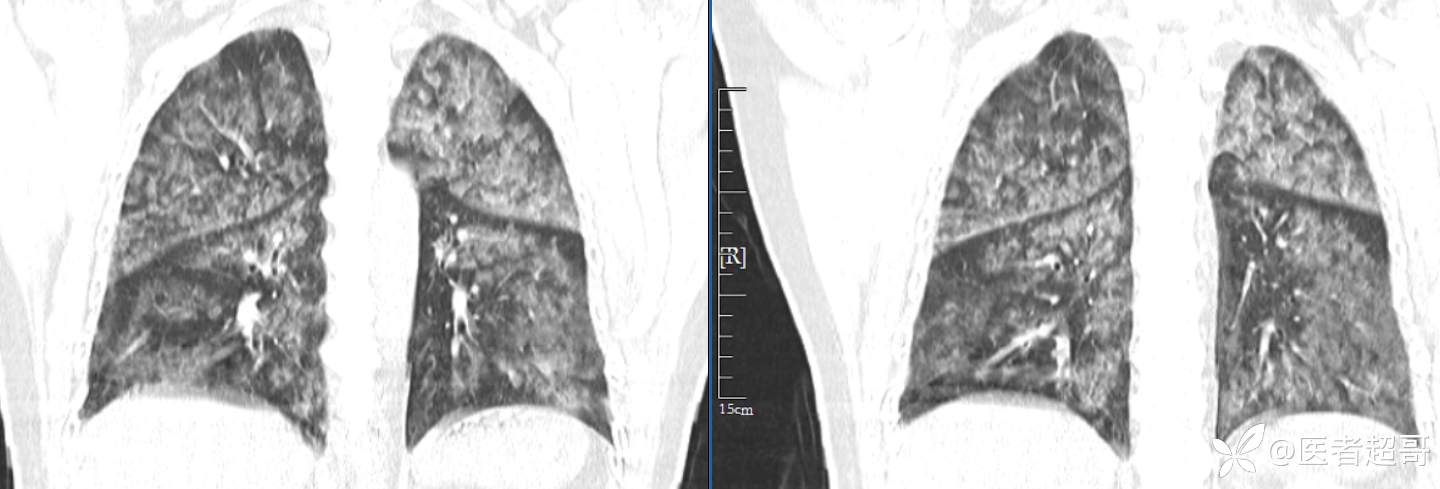

患者性别:女

患者年龄:47岁

主诉:胸痛就诊

简要病史:因“胸痛就诊”,行冠脉CTA检查,数小时后出现高热,伴畏寒寒战、气喘,暗红色泡沫样痰。

急性肺水肿 (17)